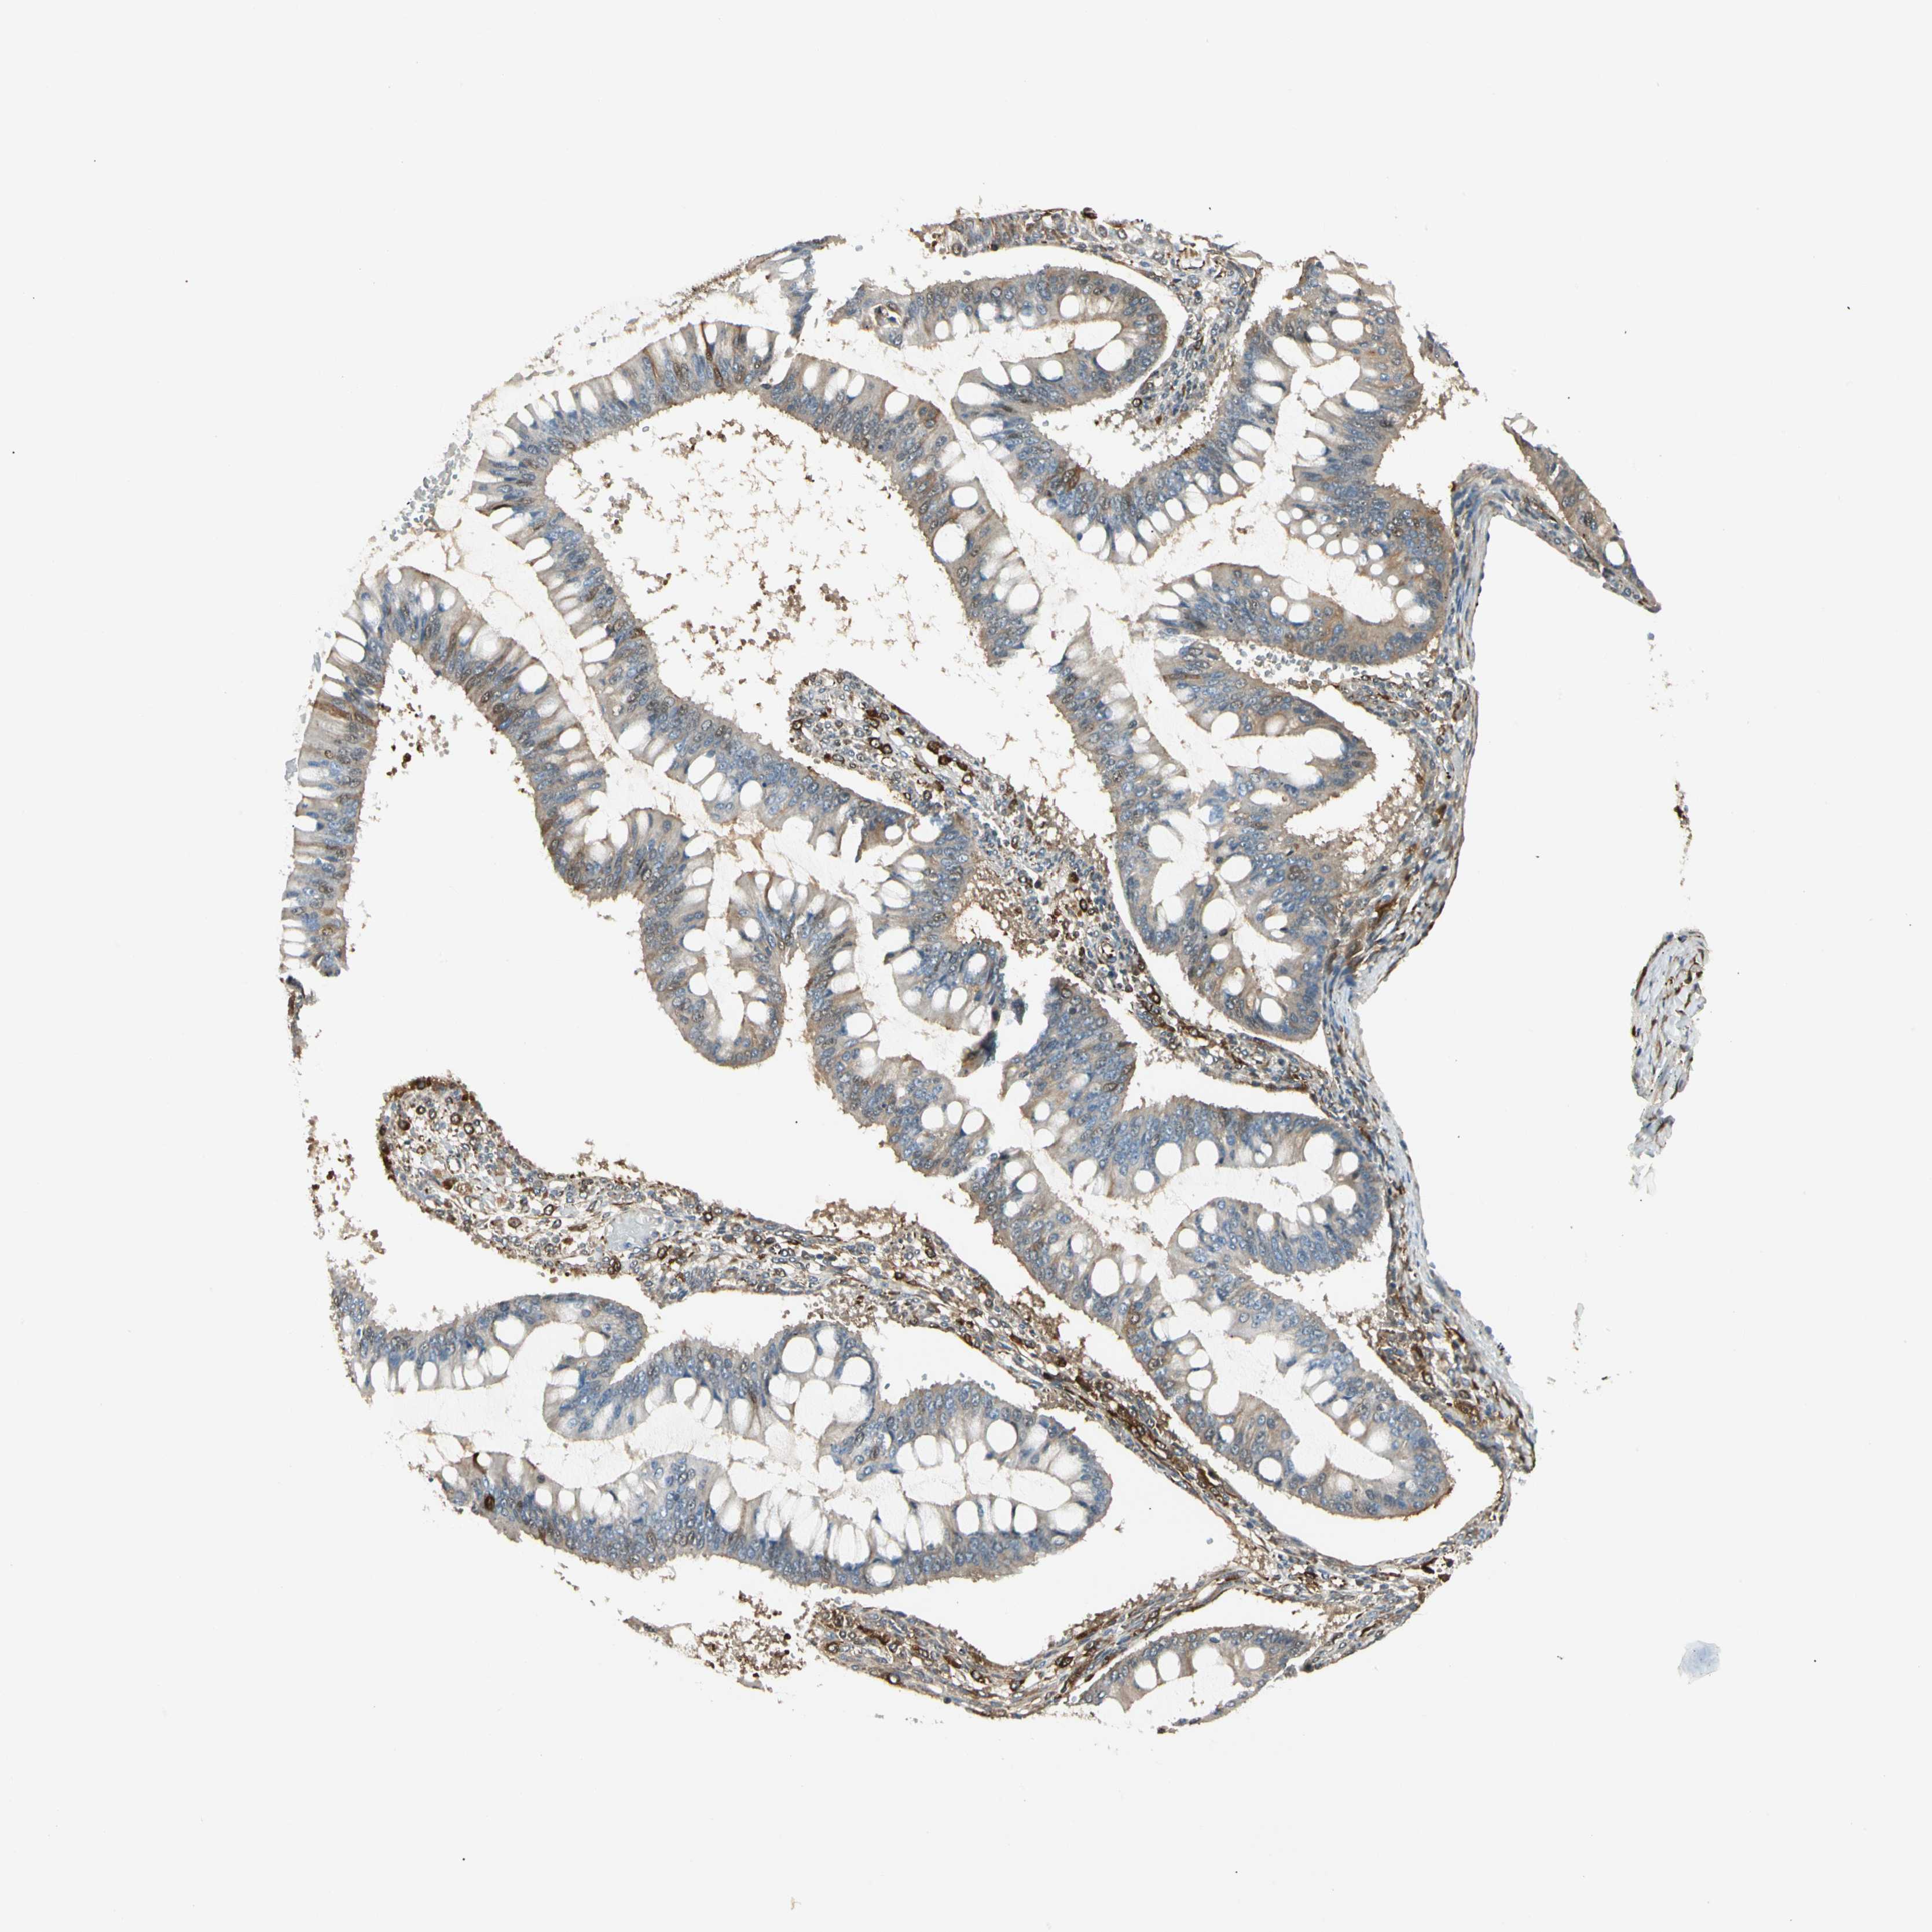

OVARIAN CANCER - Protein expressioni

A mouse-over function shows sample information and annotation data. Click on an image to view it in a full screen mode. Samples can be filtered based on level of antibody staining by selecting one or several of the following categories: high, medium, low and not detected. The assay and annotation is described here.

Note that samples used for immunohistochemistry by the Human Protein Atlas do not correspond to samples in the TCGA dataset.

Antibody stainingi

Antibody staining in the annotated cell types in the current human tissue is reported as not detected, low, medium, or high, based on conventional immunohistochemistry profiling in selected tissues. This score is based on the combination of the staining intensity and fraction of stained cells.

Each image is clickable and will lead to virtual microscopy that enables deeper exploration of all samples and also displays staining intensity scores, fraction scores and subcellular localization as well as patient and tissue information for each sample.

Antibody CAB008623

Cystadenocarcinoma, serous, NOS

Carcinoma, endometroid

Cystadenocarcinoma, mucinous, NOS

Carcinoma, NOS